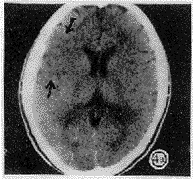

图4 左偏瘫5h,CT平扫显示右额颞皮质呈楔形密度减低与白质一致(皮质征)(a),33h复查,局部呈明显低密度影(b)。

幕上209例,大脑中动脉供血区197例,大脑前动脉供血区8例,大脑后动脉供血区4例,右小脑半球1例。CT征象阴性40例,致密动脉征表现为平扫CT图像上脑动脉密度增高,超过脑皮质密度,低于钙化密度。豆状核征表现为豆状核轮廓模糊,密度与脑白质一致或稍低(图1)。脑岛带征表现为脑岛带区灰白质界面模糊,灰白质密度一致(图2)。低密度灶分腔隙性(<1cm为小腔梗,1~1.5cm大腔梗)和片状(>1.5cm)。占位征表现为邻近脑室、脑池、脑沟变小(图3)。皮质征表现为皮质局限性密度减低,与脑白质密度一致(图4)。各征象在不同时间出现率见表1,敏感性等指标测定结果见表2。